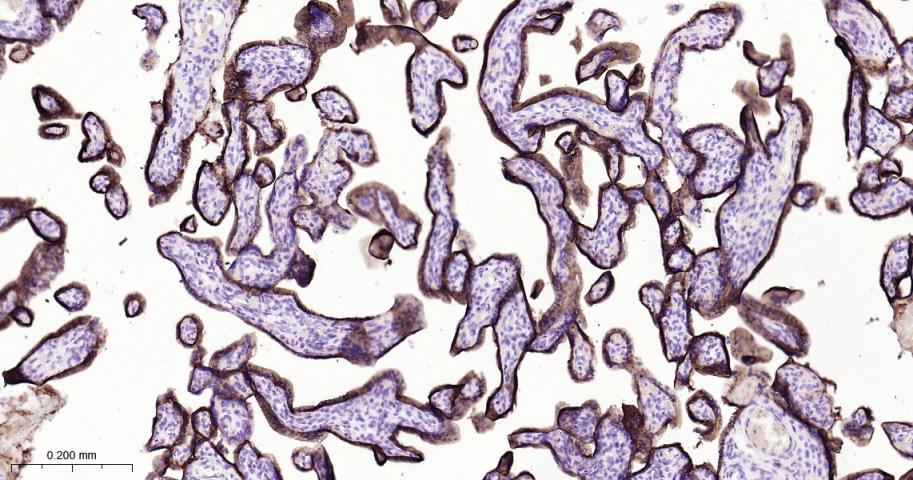

IHC-PHuman1:100-500

Expressed by all types of trophoblasts as early as 9 weeks of development. Specific for trophoblastic cells except for amniotic epithelium. In adult tissues, the expression is limited to a few epithelial cell types but is found on a variety of carcinoma.